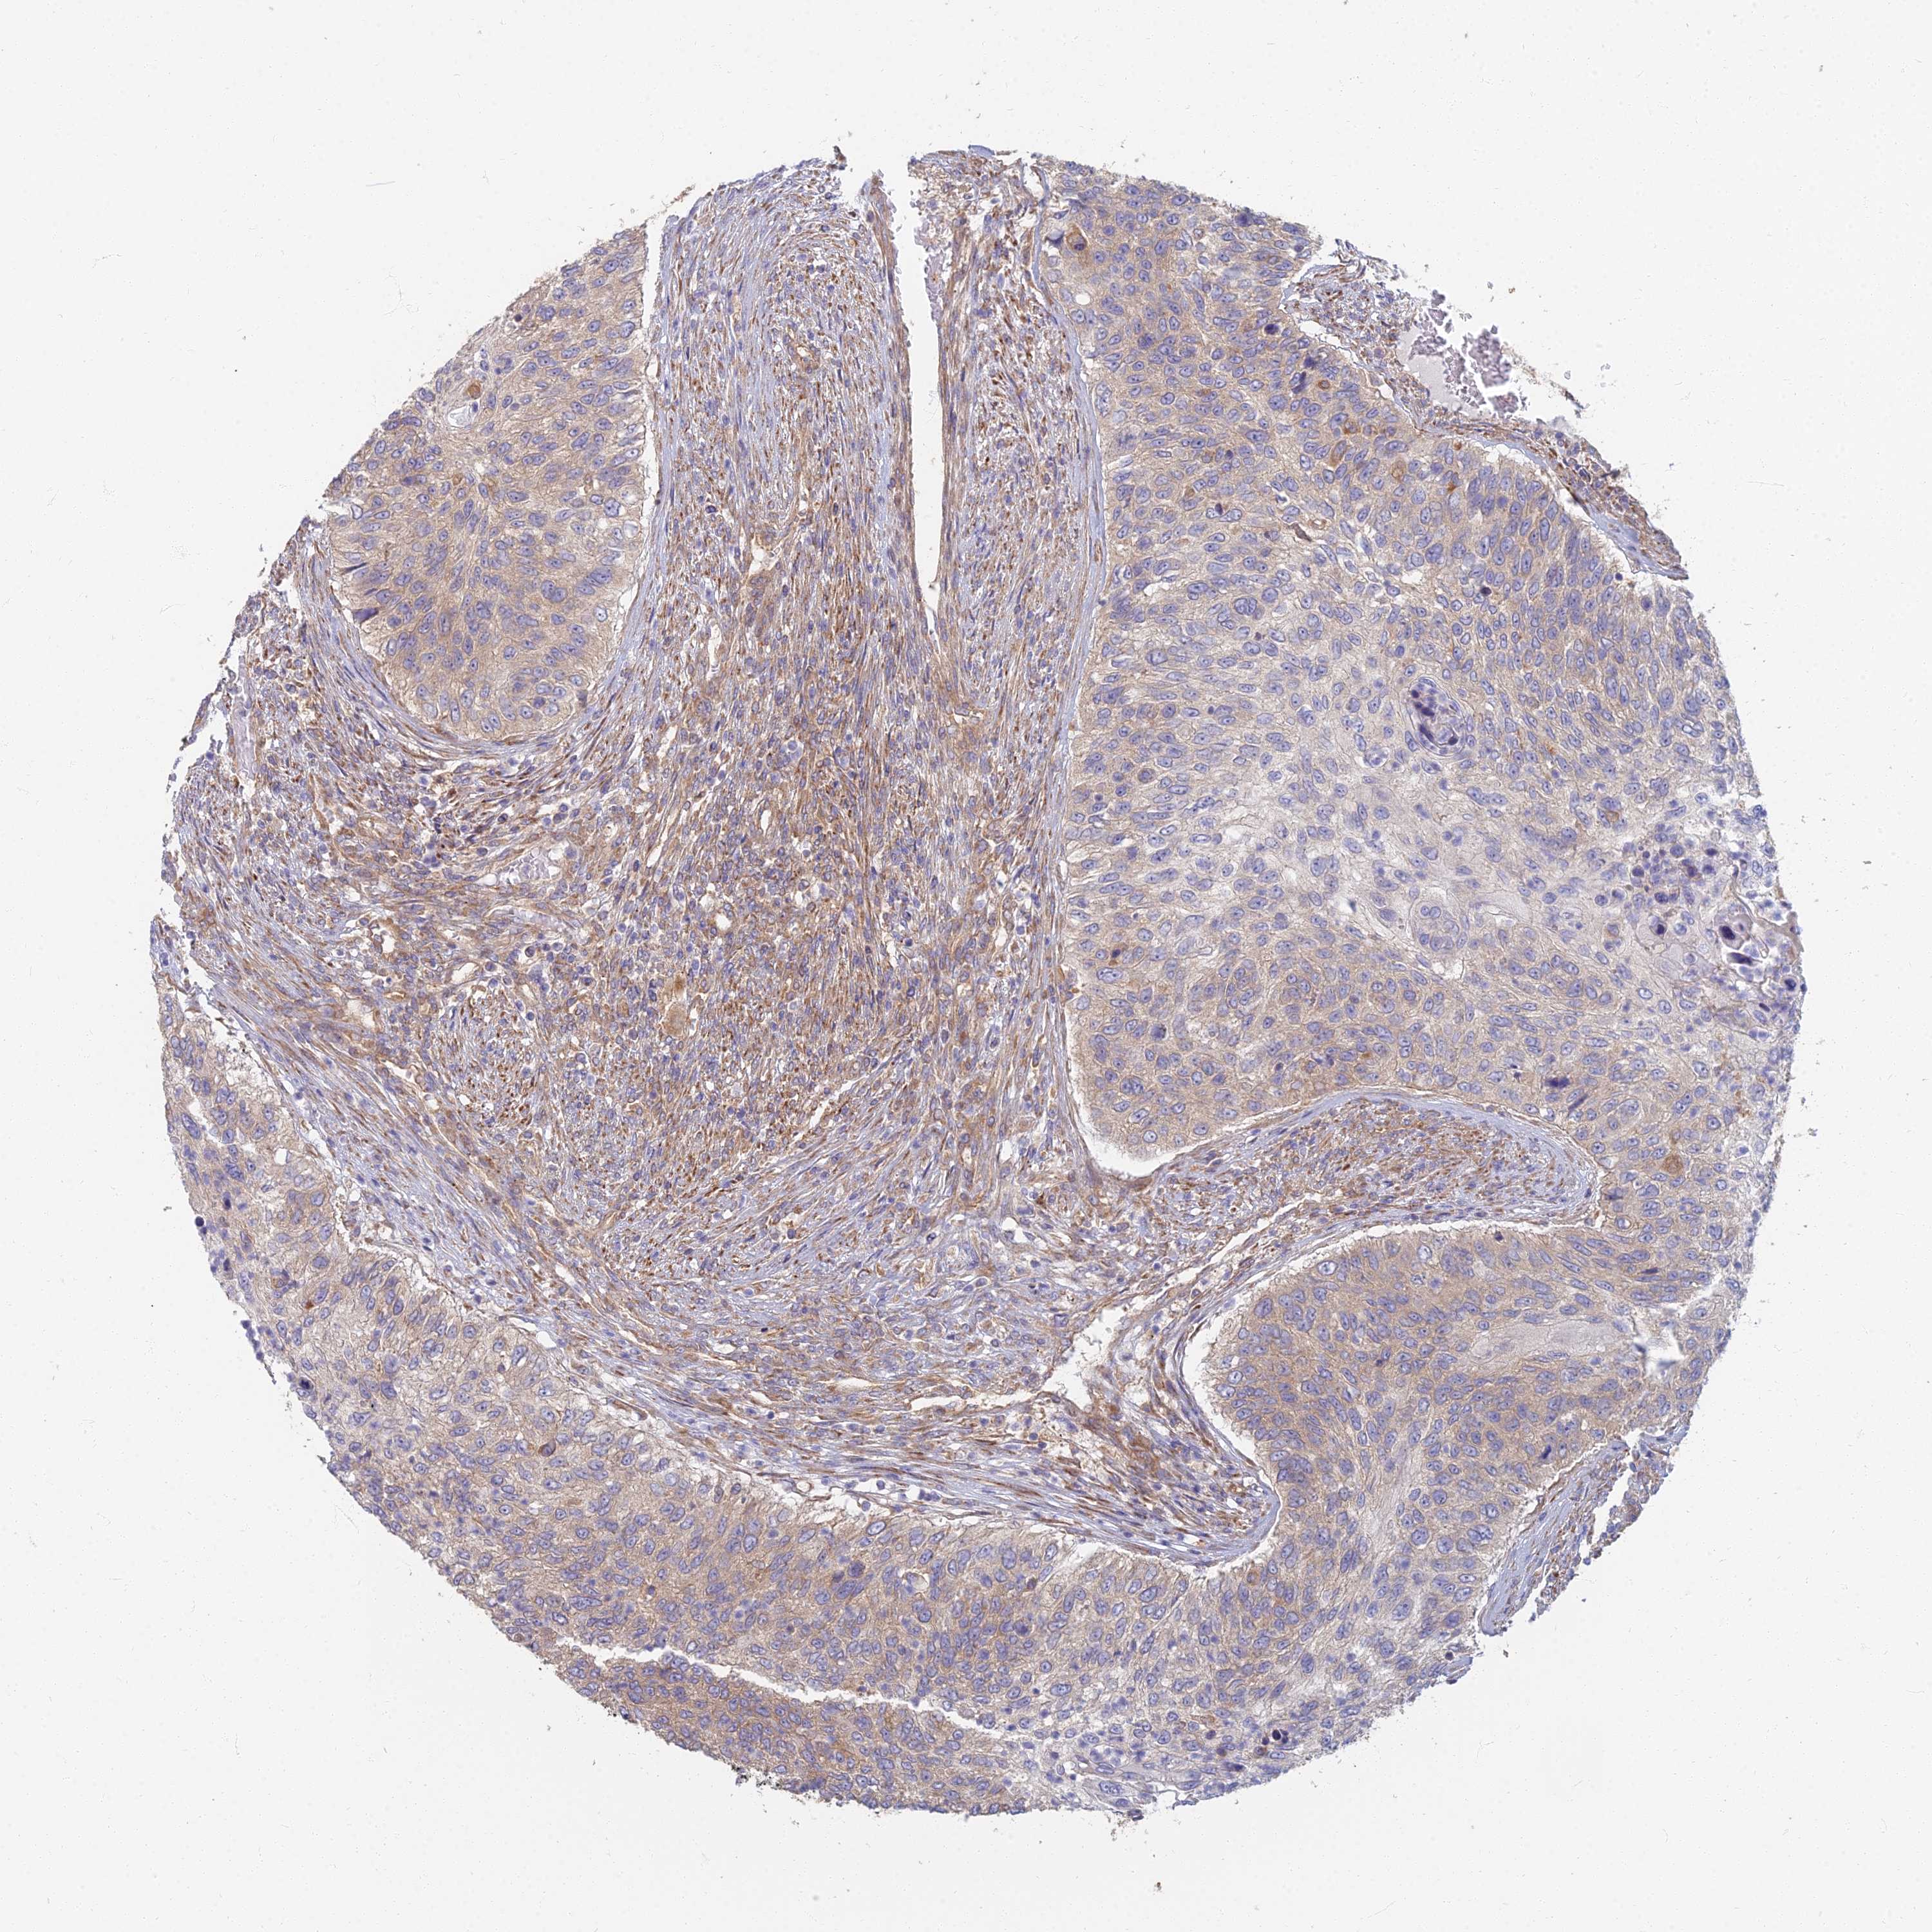

UROTHELIAL CANCER - Protein expressioni

A mouse-over function shows sample information and annotation data. Click on an image to view it in a full screen mode. Samples can be filtered based on level of antibody staining by selecting one or several of the following categories: high, medium, low and not detected. The assay and annotation is described here.

Note that samples used for immunohistochemistry by the Human Protein Atlas do not correspond to samples in the TCGA dataset.

Antibody stainingi

Antibody staining in the annotated cell types in the current human tissue is reported as not detected, low, medium, or high, based on conventional immunohistochemistry profiling in selected tissues. This score is based on the combination of the staining intensity and fraction of stained cells.

Each image is clickable and will lead to virtual microscopy that enables deeper exploration of all samples and also displays staining intensity scores, fraction scores and subcellular localization as well as patient and tissue information for each sample.

Antibody HPA044878

Staining

High

Medium

Low

Not detected

Intensity

Strong

Moderate

Weak

Negative

Quantity

>75%

75%-25%

<25%

None

Location

Nuclear

Cytoplasmic/membranous

Cytoplasmic/membranous,nuclear

Urothelial carcinoma, High grade

Urothelial carcinoma, Low grade